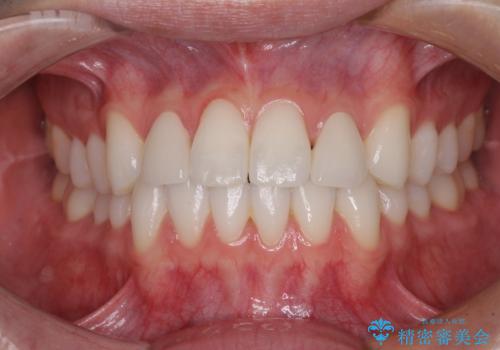

ホワイトニングを併用し、治療前と比べて自然でとても明るい口元となりました。